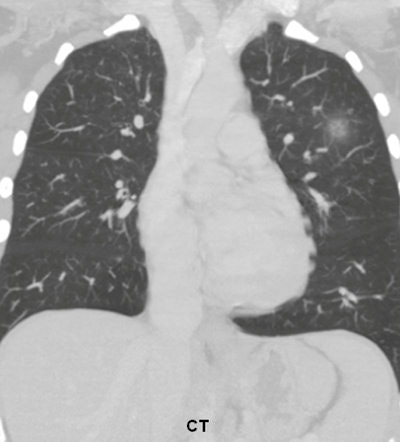

Two radiologists who did not participate in the observer study selected 36 patients (19 men and 17 women with a mean age of 52) with 46 focal pneumonias from a radiology department teaching file produced from clinical cases at the University of Chicago Medical Center from January 2004 to March 2010. Cases were chosen due to the presence of unequivocal but subtle pneumonia.

The 46 pneumonias were present on 25 standard posteroanterior (PA) and 11 portable anteroposterior (AP) chest x-rays; the mean diameter for the focal opacities ranged from 12 to 60 mm with a mean of 28 mm. The researchers also included 20 control subjects without focal pneumonia on 15 PA and five portable AP chest x-rays.

"Focal pneumonias were frequently difficult to detect on the standard [chest x-rays] but were relatively more conspicuous, and therefore easier to detect on the [bone-suppression imaging] images," the authors wrote.